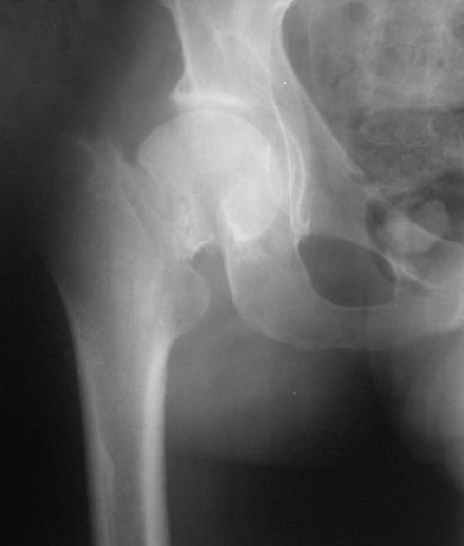

При явно выраженном варусе и флексионных состояниях после сросшихся переломов шейки бедра у молодых рекомендуется реконструктивная операция по исправлению варуса для предотвращения раннего деформирующего артроза, приводящего в результате переднего импинжмента, как показано на снимке.

Межвертельная вальгусная остеотомия представляет наименьший риск среди всех реконструктивных операции в проксимальной части бедра, создавая наилучшие биомеханические условия (увеличивается сила абдукторов, увеличивается сила суставной реакции, уменьшение рычага моментов абдукторов и уменьшение скольжения) и при меньшем риске повреждения кровоснабжения головки, где обычно в 90% случаях достигается отличный результат при применении метода для лечения ложных суставов шейки бедра.

По моему, 120 градусная угловая пластина blade plate решит все проблемы, только необходим предварительный расчет угла остеотомии, и во время фиксации пластины не забыть латерализацию бедра, иначе ось конечности от варуса перейдёт в нежелательный вальгус.

Для предупреждения вальгуса клинок пластины берется на 10-12 мм длиннее чем предварительный туннель на головке, тогда во время

фиксации за бедро пластина автоматически приблизит бедро и происходит латерализация бедра. Если между клинком и латеральным кортексом бедра положить частицу кости от остеотомии тогда образуется дополнительная компрессия на фокусе несращения.

Здесь мои диаграммы для расчета угла остеотомии и латеризации бедра.